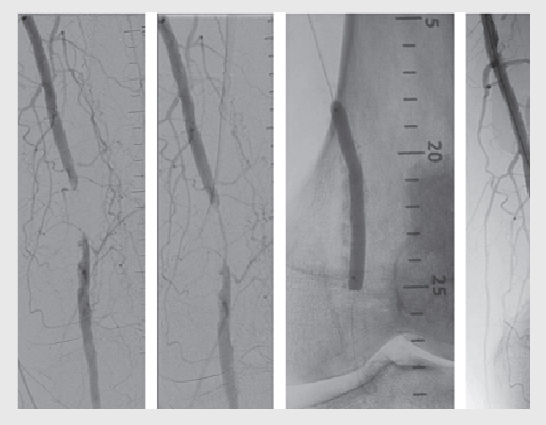

- Angioplasty and stenting: In some cases, minimally invasive procedures like angioplasty (using a balloon to widen the artery) and stent placement (to keep the artery open) may be performed to improve blood flow.

- Atherectomy: As mentioned earlier, atherectomy may be used to remove plaque from the arteries and improve blood flow in certain cases.